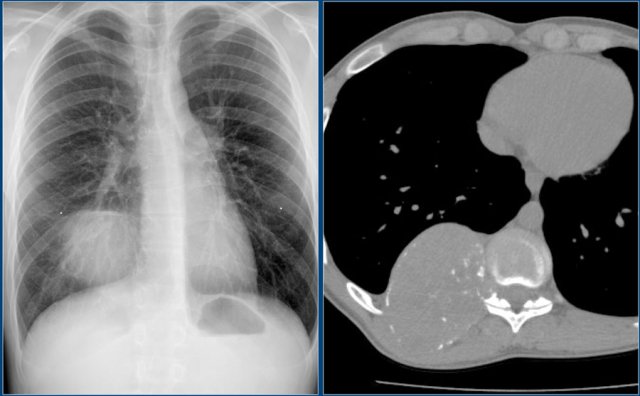

Chest X-ray shows non-specific soft tissue mass in the right lower lobe.

CT shows the mass extending from the posterior chest wall, with irregular calcifications, consistent with chondrosarcoma.

Diagnosis: high grade chondrosarcoma.